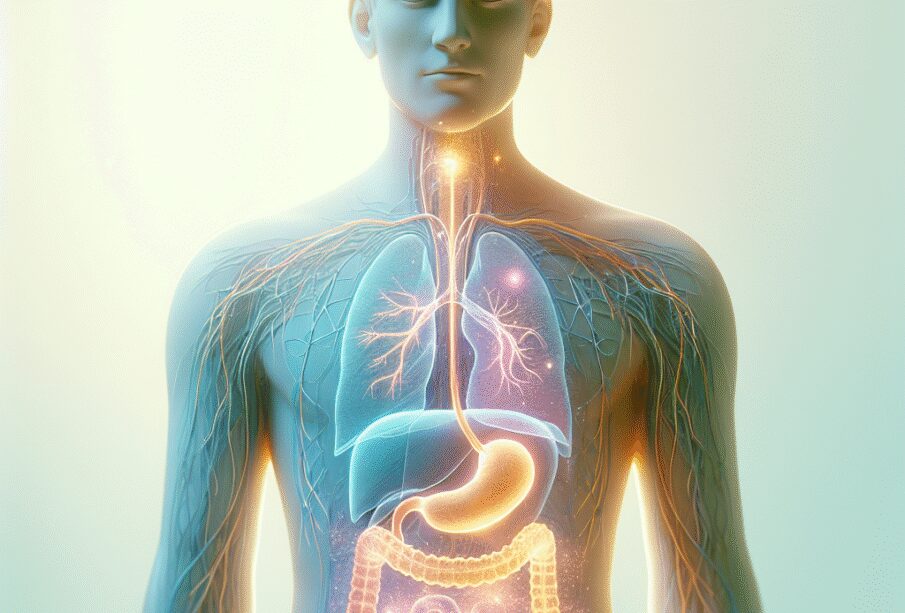

Το φούσκωμα στην κοιλιά αποτελεί έναν από τους πιο συχνούς δείκτες διαταραχής της πέψης, ενώ μπορεί να υποδηλώνει διαφορετικές καταστάσεις του οργανισμού. Πολλοί θεωρούν ότι σχετίζεται αποκλειστικά με συγκεκριμένες τροφές, αλλά η μόνιμη ή επαναλαμβανόμενη αίσθηση φουσκώματος ενδέχεται να συνδέεται όχι μόνο με πεπτικά αίτια, αλλά και με το νευρικό σύστημα. Πρόσφατες επιστημονικές μελέτες υποδεικνύουν στενή σχέση ανάμεσα στη νευρική ευαισθησία, το άγχος ή την ψυχολογική πίεση και την εμφάνιση φουσκώματος. Στο παρόν κείμενο θα παρουσιαστεί πώς το έντονο ή επίμονο φούσκωμα σχετίζεται με ένα ευαίσθητο νευρικό σύστημα, ο ρόλος της ψυχικής κατάστασης στην έναρξη του συμπτώματος καθώς και χρήσιμες πρακτικές για την ανακούφιση αυτής της δυσφορίας.

Η σχέση νευρικού συστήματος και πεπτικού

Υπάρχει άμεση και διαρκής επικοινωνία μεταξύ εγκεφάλου και εντέρου μέσω του άξονα εγκεφάλου–εντέρου. Η ροή πληροφοριών είναι αμφίδρομη: το κεντρικό νευρικό σύστημα επηρεάζει άμεσα τη λειτουργία του εντέρου, ενώ το πεπτικό μεταδίδει μηνύματα πίσω στον εγκέφαλο. Όταν το νευρικό σύστημα είναι πιο ευαίσθητο ή το επίπεδο του στρες αυξάνεται, αυτή η αλληλεπίδραση γίνεται περισσότερο έντονη.

Γιατί το ευαίσθητο νευρικό σύστημα προκαλεί φούσκωμα

Άτομα με ευαίσθητο ή πιο ευάλωτο νευρικό σύστημα συχνά αντιδρούν πιο έντονα σε καθημερινό άγχος ή δυσκολίες. Ακόμη και απλά γεγονότα, όπως μια δημόσια εμφάνιση, μια εξέταση ή μια πιεστική εργασία, μπορούν να εντείνουν τη νευρική ένταση. Σε αυτές τις περιπτώσεις, ενεργοποιούνται περιοχές του κεντρικού νευρικού συστήματος που παράγουν ορμόνες στρες, όπως η κορτιζόλη, επιδρώντας ισχυρά στο πεπτικό: προκαλείται μεταβολή στην κινητικότητα του εντέρου, συχνότερη κατάποση αέρα (ψυχογενής εισρόφηση αέρα) και αλλοίωση της οξύτητας του στομάχου. Έτσι προκύπτει η δυσάρεστη αίσθηση φουσκώματος και πίεσης, ακόμη και όταν τα επίπεδα αερίων στο έντερο είναι ελάχιστα αυξημένα.